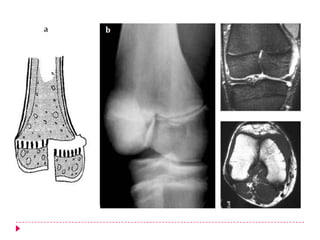

   FRACTURA DEL PILÓN TIBIAL

   Una fractura del pilón afecta a la superficie articular de la

tibia.

   Tipo I. Fractura no desplazada, en forma de T de la parte distal

de la tibia que se extiende a la articulación

   Tipo II . I + desplazamiento de los componentes

intraarticulares

   Tipo III. Fractura compleja, intraarticular, multifragmentaria.

   Tipo V. Extensión Diafisiaria

   Tipo IV. Extensión metafisiaria

   Tratamiento. Reducción quirúrgica y estabilización del

peroné + Yeso + Movilización temprana